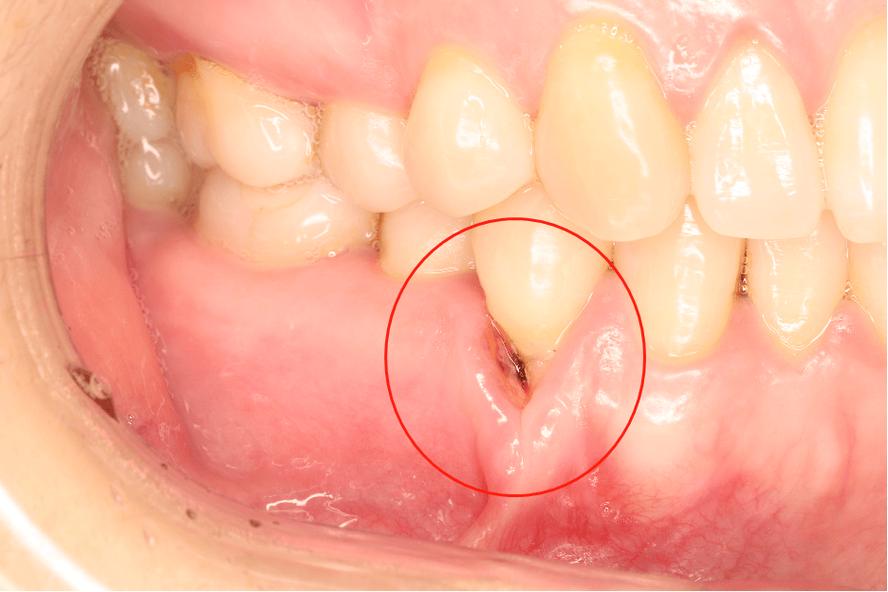

- 牙龈退缩:最直接的表现,下牙牙龈边缘低于釉牙骨质界,牙根暴露,严重时可达根中1/3或更。

- 美学影响:下前牙牙龈退缩后,可能形成“黑三角”(牙间乳头退缩导致牙缝暴露),影响微笑美观。

- 牙周健康异常:常伴随牙龈红肿、出血(牙龈炎)、牙周袋形成(若合并牙周炎)、牙槽骨吸收(影像学可见骨密度降低、骨 height 下降)。